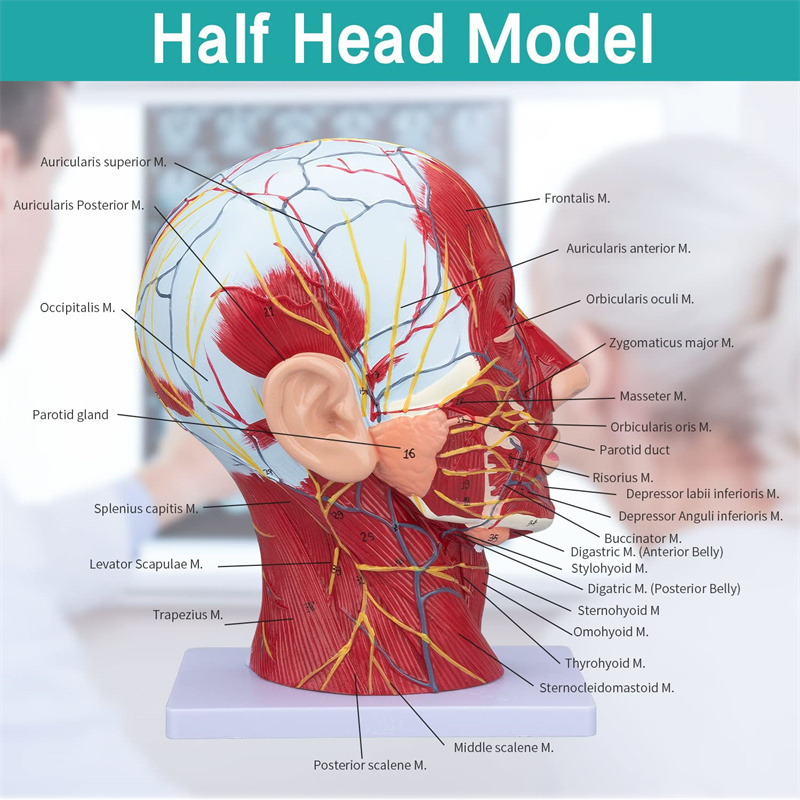

Human Half Head & Neck Anatomy Model Superficial Neurovascular Model

Human Half Head & Neck Anatomy Model Superficial Neurovascular Model

| Features | The model shows the local morphology of the inner and outer sides of the Median sagittal section of the head and neck, as well as the structures of blood vessels and nerves, and there are 84 parts indicating signs in total. |

【1:1 Lifesize】Median Section of 1:1 natural large head & neck superficial neural vascular muscle model (right side). Fine workmanship. Offering a full range of anatomical features.

【Superficial Neurovascular Muscle Model】Highly detailed, numbers marked, detachable ear, deepen the understanding of the superficial muscles, vessels, nerves and the internal structures of the head & neck. Red-artery, blue-vein, yellow-nerve.

【Features】It shows the superficial muscles of the exposed face; the superficial blood vessels & nerves of the face & scalp; the inner structures of parotid gland & upper respiratory tract; the sagittal cross-section structure of the cervical spine.

This model shows details of the right head neck and mid sagittal section of the human. including the superficial

muscles of the exposed face; the superficial blood vessels and nerves of the face and scalp; the inner structures

of parotid gland and upper respiratory tract; the sagittal cross-section structure of the cervical spine.

The model showed the local morphology of the medial and lateral sagittal sections of the head and neck and its vascular and nerve structures, with a total of 100 site indicators.

This model is a natural large head and neck superficial neurovascular muscle model, 1 component, showing the details of the human right head and neck and median sagittal section, including the exposed superficial muscles of the face, superficial vessels of the face and scalp, nerves and the medial structure of the parotid gland and upper respiratory tract, and the sagittal section structure of the cervical spine